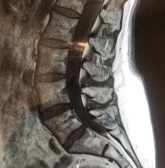

Röntgen

Ibland vill kiropraktorn komplettera undersökningen med röntgenbilder. Orsaken till detta är:

- Att bedöma skicket på diskarna ("stötdämparna" mellan kotorna).

- Att bedöma graden av degeneration (= förslitning).

- Att lokalisera potentiella problemområden.

- Att utesluta patologier (= sjukdomar) som kontraindicerar (= olämpliggör) kiropraktisk behandling.

Att se är att veta, att inte se är att gissa. Det är inte önskvärt att gissa när det gäller din hälsa.

Till skillnad från en ryggröntgen inom den traditionella vården så vill Gonstead kiropraktorn ha viktbärande bilder, dvs bilder där patienten står upp.

Orsaken till detta är kroppen verkar i upprättstående och belastning på ryggraden och dess strukturer bäst utvärderas i denna position. Ryggradens naturliga böjningar (halsryggs- och ländryggslordos samt bröstryggskyfos) samt krökningar i ryggraden (= scolios) ser annorlunda ut i viktbärande ställning jämfört med liggande. Även bäckenet ser annorlunda ut i viktbärande jämfört med liggande.